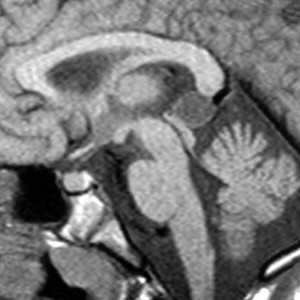

Нейроглиальная киста

Нейроглиальная киста (син. глиоэпендимальная киста, нейроэпителиальная киста) - это редкое доброкачественное кистозное образование центральной нервной системы выстланное эпителием. При визуализации представляет собой округлое образование с гладкими ровными контурами, с содержимым соответствующим по характеристикам спинномозговой жидкости, с минимальными изменениями окружающей ткани [1].

Нейроглиальные кисты являются врожденными образованиями располагающимися в белом веществе, они образуются за счет секвестрации элементов нервной трубки в эмбриональном периоде с формированием заполненной жидкостью полости выстланной глиальными клетками [3].

Обычно представляют собой четко отграниченные не усиливающиеся гиподенсивные образования с плотностью соответствующей плотности спинномозговой жидкости, как правило единичные, без перифокального отека, кальцинатов или признаков объемного воздействия.

Нейроглиальные кисты по сигнальным характеристиками соответствуют спинномозговой жидкости, и имеют гипоинтенсивный сигнал на Т1 изображениях, и гиперинтенсивный сигнал на Т2 изображениях, как правильно с подавлением сигнала на FLAIR последовательностях.

Дифференциальный диагноз

- порэнцефалическая киста

- имеется связь с боковым желудочком

- окружена зоной глиоза

- как правило располагается экстрааксиально

- как правило множественные

- часто в виде скоплений в области базальных ганглиев

- как правило

- частичное контрастное усиление

- иногда сложно дифференцировать

- локализуется перивентрикулярно

- не соответствует СМЖ на всех последовательностях

- имеется ограничение диффузии